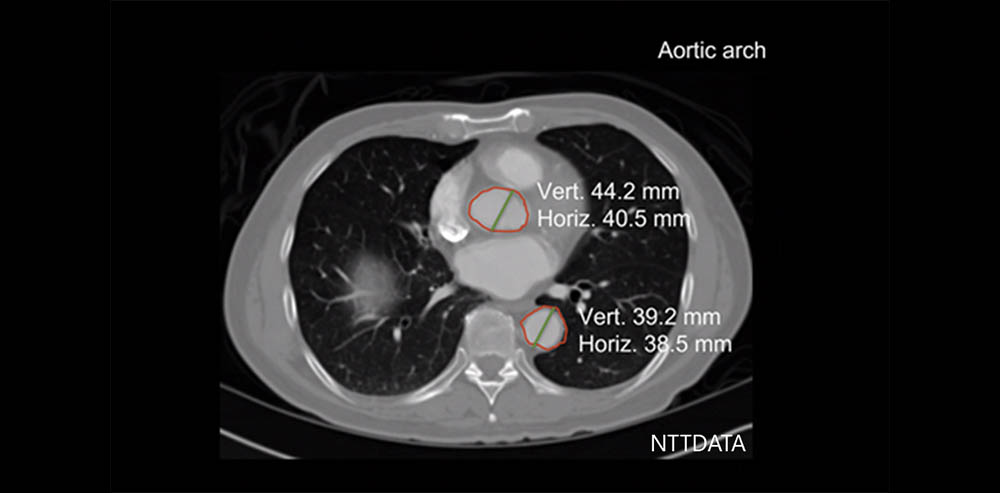

医療業界において、内視鏡やレントゲン写真などによって、人間の体内環境をデータ化することで可視化し、それに基づいて診断を行うということが広く行われてきました。データ化された情報に基づいて診断するという行為は、AIの得意分野そのものであり、現在、医療分野における画像診断が普及しつつあります。

こちらの画像では、AIが自動でCT画像を分析し、各臓器や部位のセグメンテーションを行い、それにより医療の効率化に寄与しています。